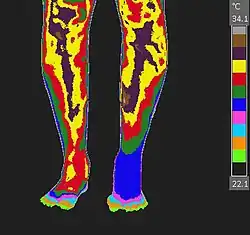

Non-contact thermography, thermographic imaging, or medical thermology is the field of thermography that uses infrared images of the human skin to assist in the diagnosis and treatment of medical conditions. Medical thermology is sometimes referred to as medical infrared imaging or tele-thermology and utilizes thermographic cameras. According to the American Academy of Thermology, Medical Thermology practitioners are licensed health care practitioners who utilize IR imaging in consistent with medically established paradigms of care. Non-medically licensed alternative practitioners who are not held to the same standard may offer thermography services but that should not be confused with the field of medical thermology.

Restated, medical thermology is the use of infrared (IR) imaging to assess skin temperature as an extension of the clinician's physical exam to aid in the formation of a medical diagnosis or treatment plan. Medical Thermology does not condone those who purport that "Thermography" can find disease by looking for areas of the body that have abnormal heat or irregular blood flow. IR imaging simply does not have the ability to assess temperature beyond the surface of the skin.